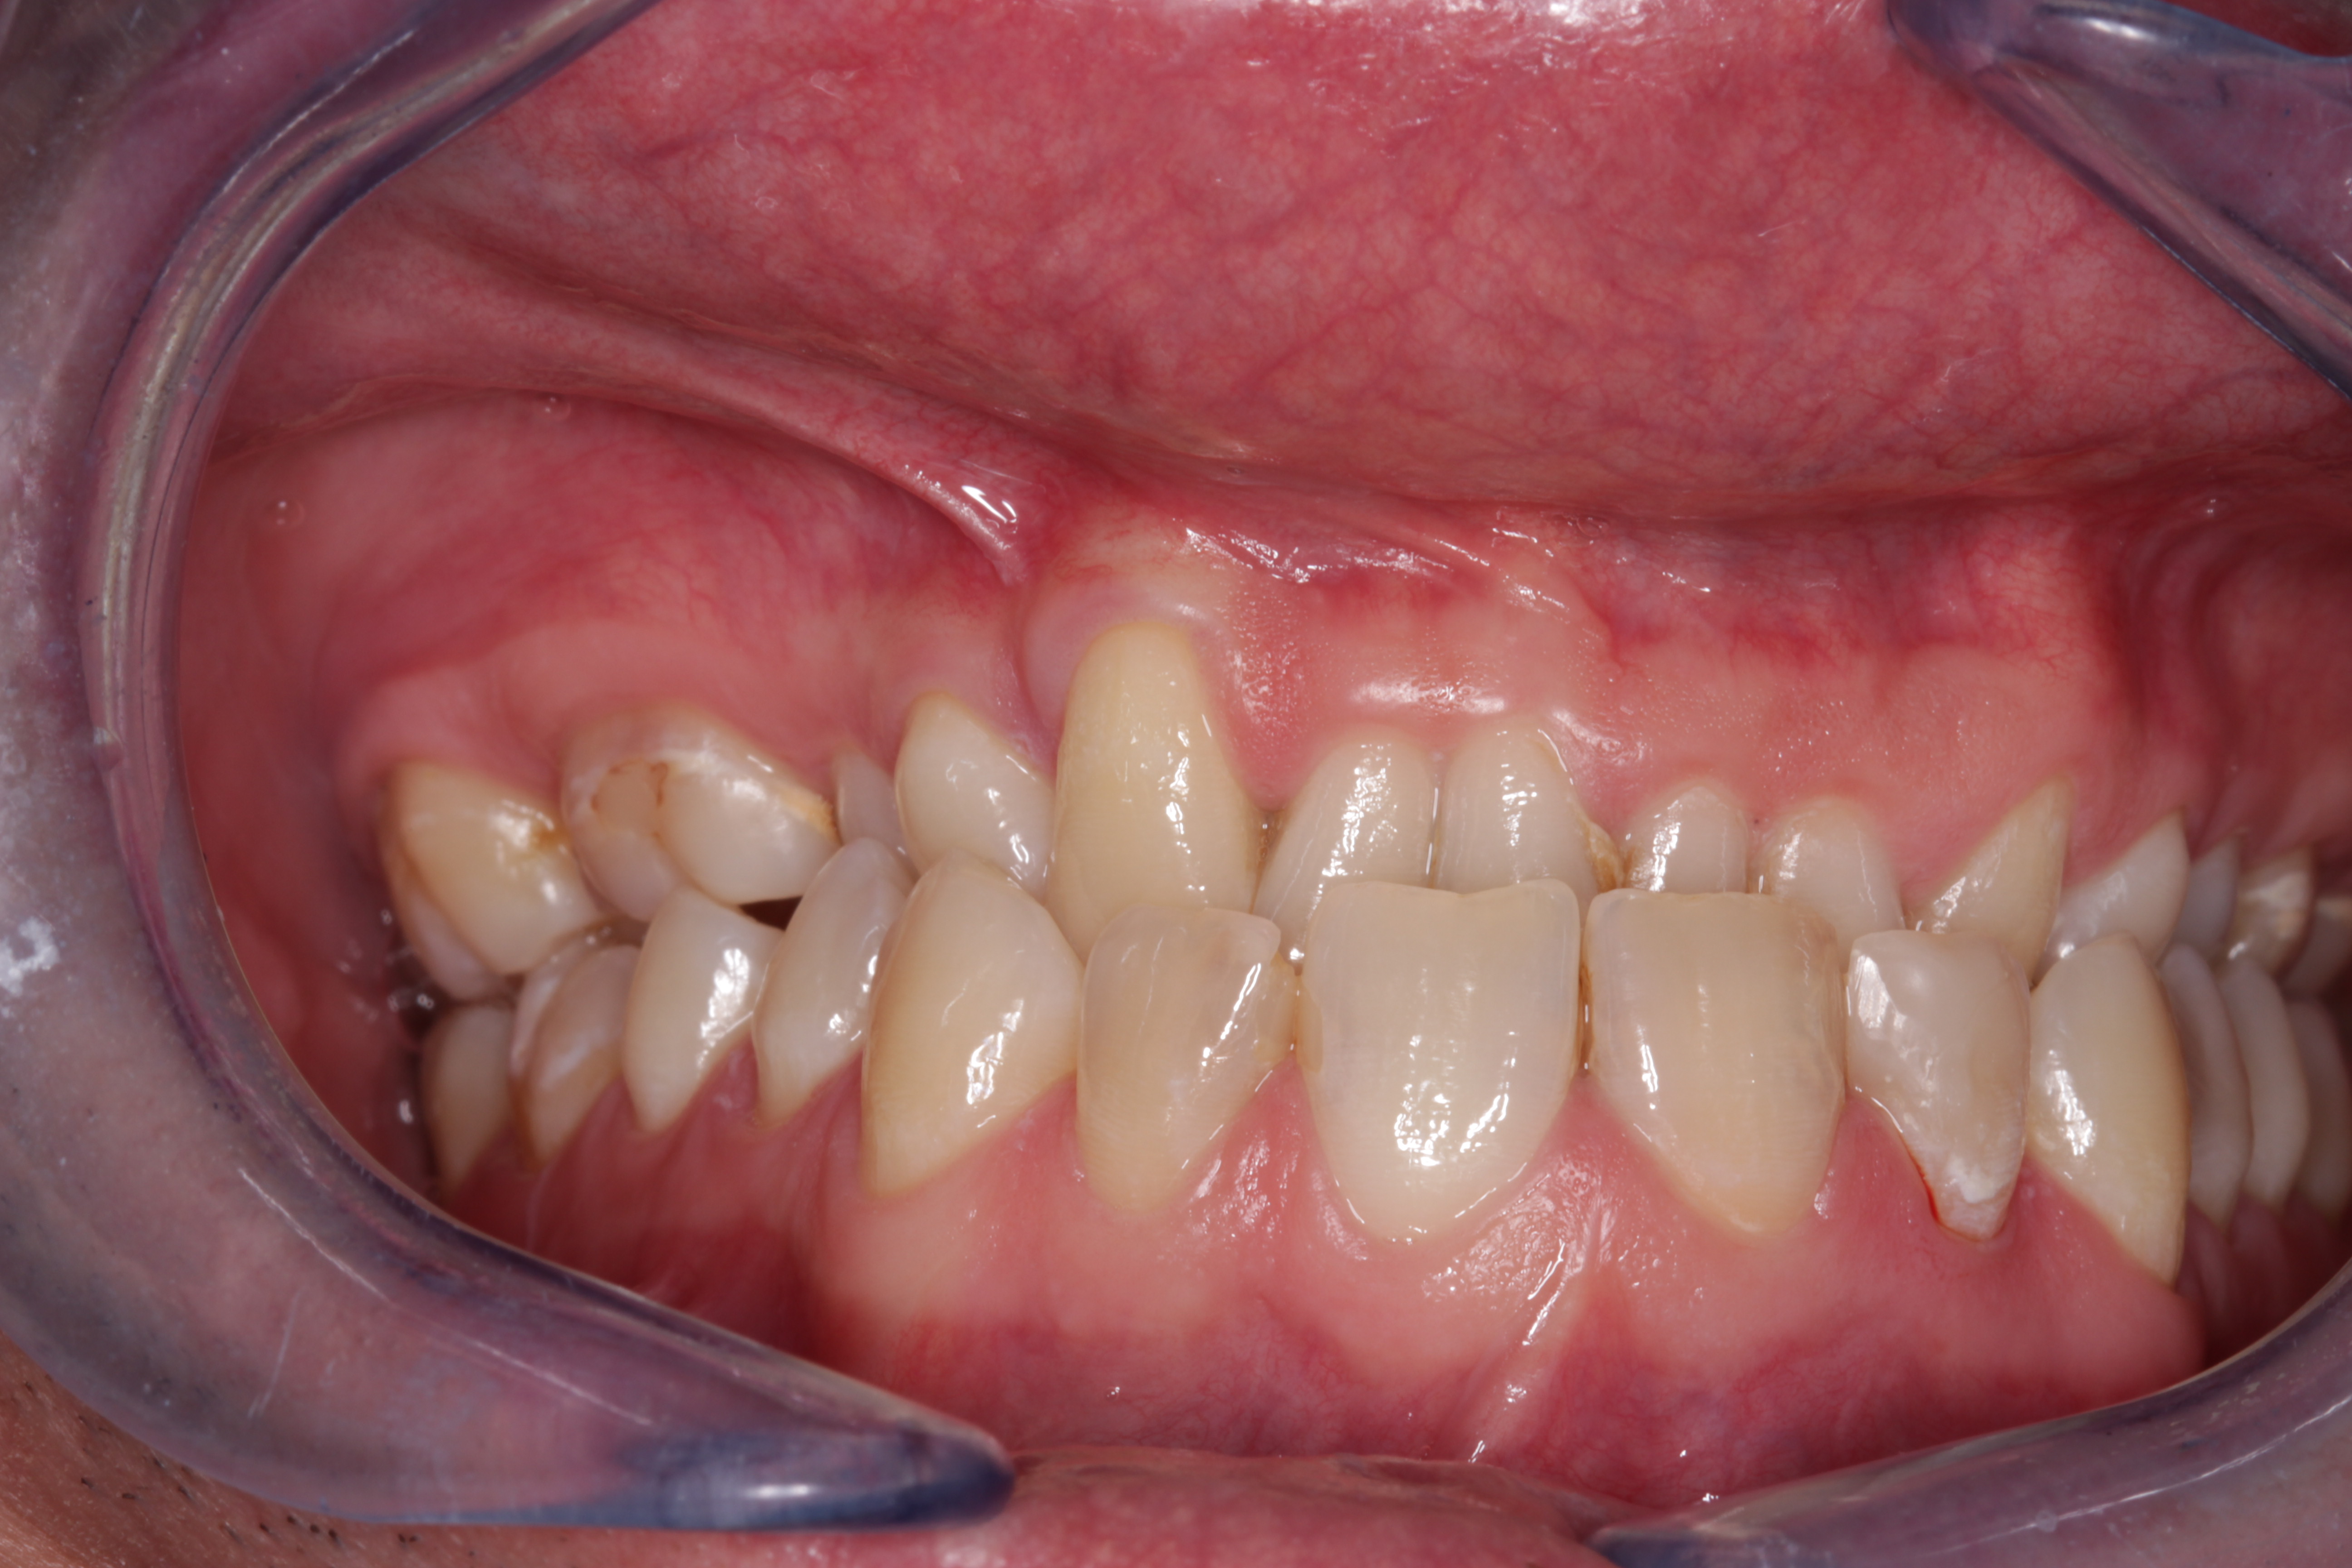

- Rehabilitación postraumática